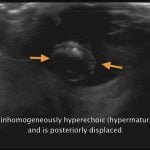

Atlas Of Small Animal Ultrasonography 2nd Edition (Videos Screenshot) 02